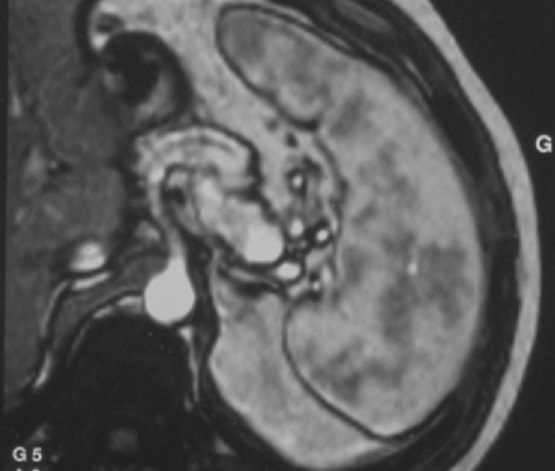

-La IRM : Methode le plus frequemment d’utilise pour

etudie la rate et se donne des images de la rate en bonne definition . L’examen doit

de organe etudie . La sequece ponderee sur T1 , T2 rapide en

apnee ( HASTE ), T2 FATSAT et avec injection de chelate de

Gadolinium intraveineuse seront intallees. Image

radiologique IRM normale de la rate

-

Les sequences de

image en ponderation T2 la rate est hyperintense

L’injection de

chelates de gadolium est necessite de explorer le temps

de rehaussement parenchymateuse tres precoce ( 15-25 sec

apres l’injection ) avec aspect de la rate heterogene et

puis rapidement devient homogene et isointense en

rapport avec le foie a la fin du temps de evacuation .

Aspect radiologique IRM de

la rate pondere sur T2 FatSat . La parenchyme de la

rate est homogène et tres hypersignal que le foie et

les autres organes . Image IRM T2 FATSAT coupe axial |

Aspect de la rate au temps de evacuation

apres injection de chelate de Gadolinium . Le

parenchyme de la rate est homogene et isosignal par

rapport au foie |